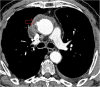

Hydatid cyst caused by the larval form of Echinococcus is a worldwide zoonosis. The lungs and liver are the most common sites involved. While the lung parenchyma is the most common site within the thorax, it may develop in any extrapulmonary region including the pleural cavity, fissures, mediastinum, heart, vascular structures, chest wall, and diaphragm. Imaging plays a pivotal role not only in the diagnosis of hydatid cyst, but also in the visualization of the extent of involvement and complications. The aim of this pictorial review was to comprehensively describe the imaging findings of thoracic hydatid cyst including pulmonary and very unusual extrapulmonary involvements. An outline is also given for the findings of complications and differential diagnosis of thoracic hydatid cyst.